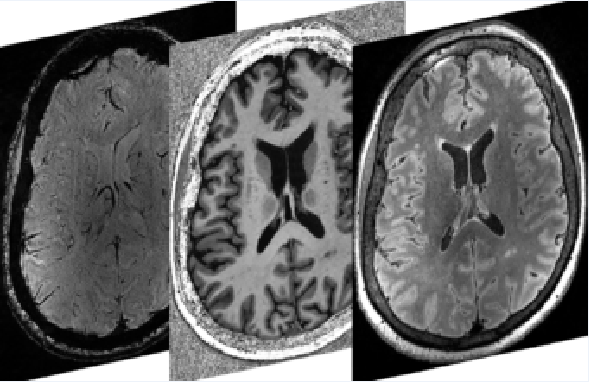

Some of these tiny brain injuries are so small that they aren’t visible with clinical brain imaging done in hospitals. However, an ultra-high-field MRI scanner at Robarts’ Centre for Functional and Metabolic Mapping is more than twice as powerful as a conventional MRI and can scan the brain in extremely high resolution.

Researchers at Robarts have developed specialized techniques to use the 7-Tesla MRI to observe even the tiniest of microbleeds. They can also pick up very subtle changes to white matter that can show where the brain has been damaged, and track changes in acidity in the brain that can indicate where it’s been deprived of oxygen.